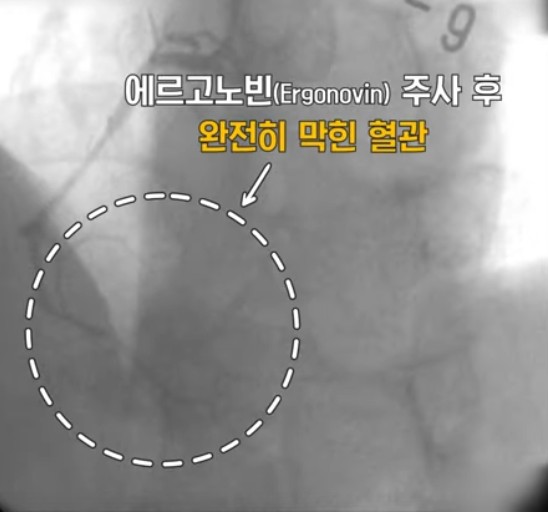

변이형 협심증을 진단하기 위해서는 경련유발검사를 시행하며 치료는 약물 치료로 대부분 증세 없이 지내실 수 있지만 대게 1년 이상 투약이 필요하고 일부 환자는 투약을 줄이거나 , 투약을 중지하는 경우도 있습니다만 평생 복용해야 하는 경우도 있습니다.

문제는 혈관이 수축(경련)하는 상태가 지속되면 급성 심근 경색증, 부정맥등의 합병증이 생기고 급성 심정사로 이어질 수 있기 때문에 위험요인이 있으시는 분은 정확한 진단과 치료를 받으시고 정기적인 검사를 하는 것이 치료와 예방에 아주 중요합니다.